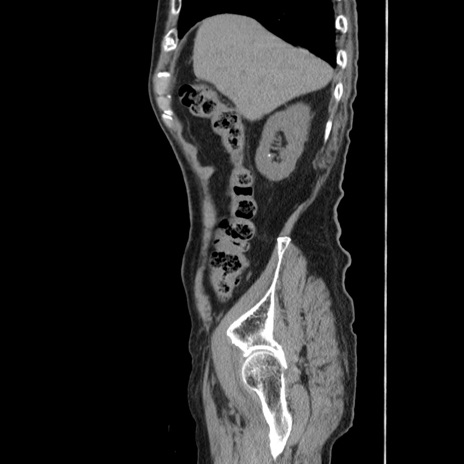

症例24(矢状断像)

【症例】80歳代男性

【主訴】左側腹部痛、嘔吐

【現病歴】本日早朝より左腹部に痛みあり。昼頃嘔吐認めたため、救急要請。

【既往歴】直腸癌(Mile手術)、胆摘

【身体所見】意識清明、BT 35.9℃、BP 221/93mmHg、SpO2 97%(RA) 、腹部:左ストーマ周囲に限局性の腹部膨隆あり。 膨隆部自発痛・圧痛あり・軟。

【データ】WBC 7700、CRP 0.09